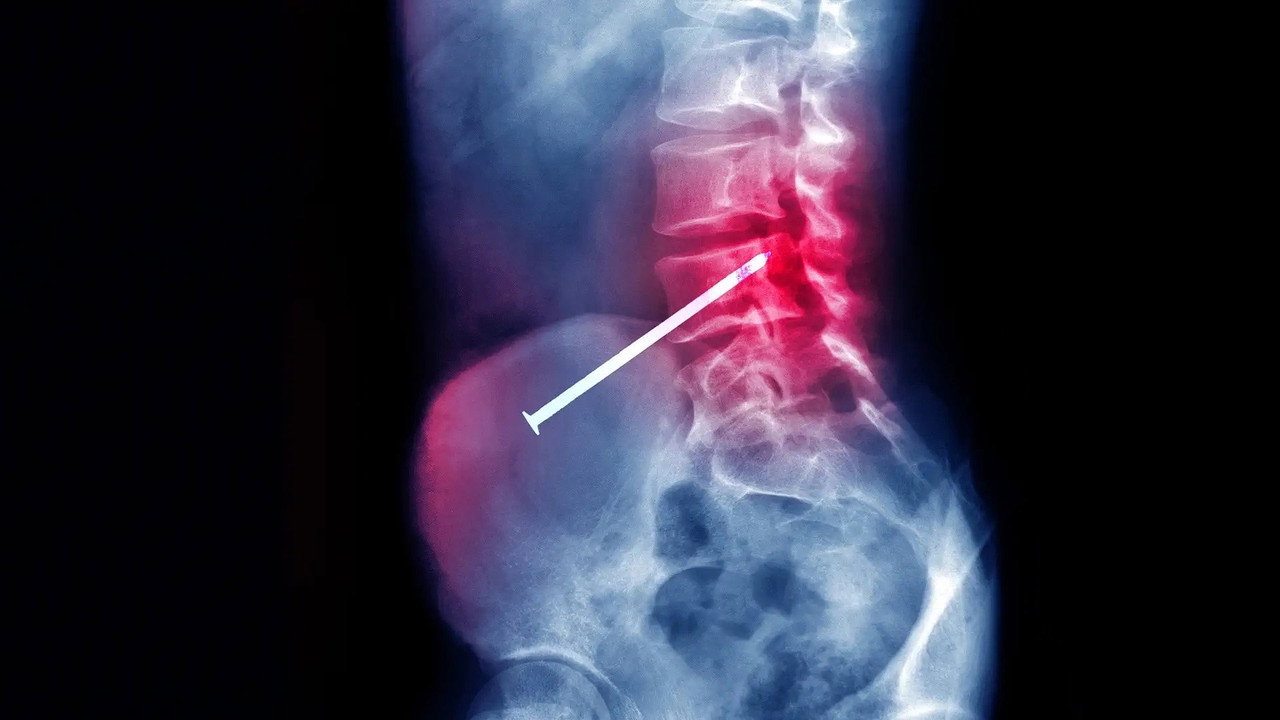

Des gens se retrouvent empalés sur des objets étonnants, et sont sauvés grâce aux compétences des médecins.